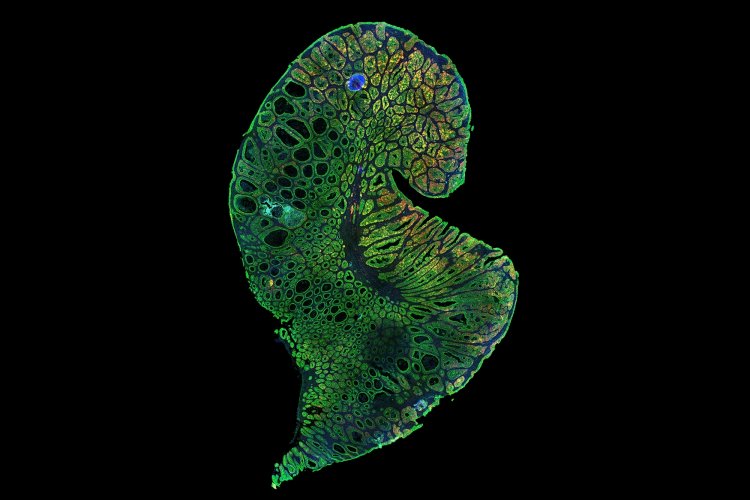

MIT Stem Cell Initiative studies focus on normal and cancer stem cells of epithelial tissues. Epithelia are one of four general tissue types in the body; they line most organs and are where the vast majority of cancers arise. Epithelial cells from different organs share some biological properties, but also have distinct differences reflecting the organ’s specific role and/or environment. In particular, the MIT Stem Cell Initiative has focused on the breast and colon, as these tissues are quite different from each other, yet each constitutes a major portion of cancer incidence.